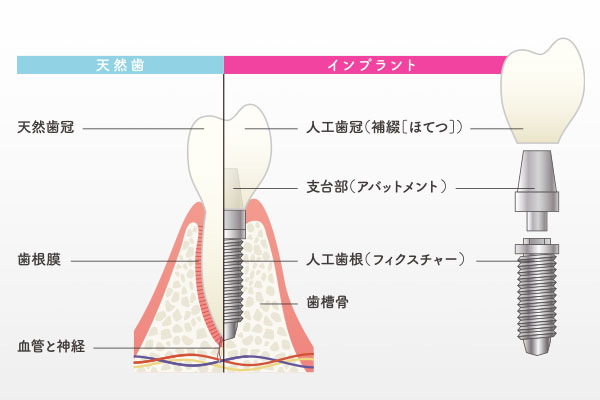

インプラント治療とは

インプラントは、歯を失った部分のあごの骨に、チタンまたはチタン合金製の人工歯根を埋め込み、それを土台として人工の歯を装着する治療です。チタンは、骨としっかり結合する性質があり、生体親和性にも優れた材質です。インプラントは、人工歯根(インプラント体)、土台(アバットメント)、人工歯(上部構造)という3つの構造から成り立っており、審美的に良好なだけではなく、周囲の歯に負担をかけることなく、しっかりと噛む機能を取り戻します。

他の治療との違い

インプラント治療の大きな特徴は、歯を「縦の力」で支えることです。ブリッジのように両隣の歯を削って連結したり、入れ歯のように残存している歯で支えたりする仕組みとは異なります。インプラントは、天然歯で噛んだときの感覚に近く、咬合力(噛む力)を約90%回復させることが可能です。一方、ブリッジは約70%、入れ歯では約40〜50%程度の回復とされています。周囲の歯に負担をかけず、自分の歯と同じように噛むことができることが最大のメリットです。